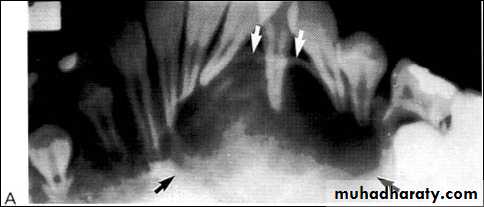

A: Radiolucent apical scar left after successful endodontic treatment..

B:New bone forming from the periphery of the

Lesion.

If the R.L.enlarged, pain,sinus,or no regression in the size of lesion after 6months (P. A. Cyst).

A

B

Apical scar